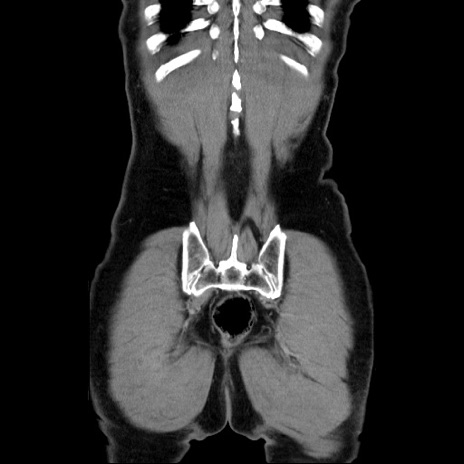

矢状断像

【症例】60歳代 男性

【主訴】右鼠径部膨隆

【現病歴】1年程前より右鼠径部膨隆あり。自己にて還納可能だったため放置していた。3時間前より右鼠径部の脱出を認め、還納困難となり受診。

【既往歴】高血圧

【身体所見】右鼠径部に小児頭大の膨隆あり。弾性硬であり、用手還納は困難。左鼠径部にも膨隆を認める。脱出はなし。